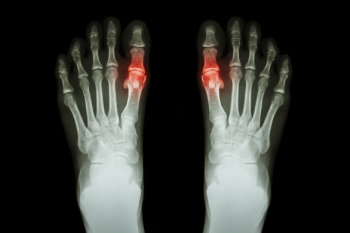

- Removing foot deformities like bunions and bone spurs

- Bunionectomy for painful bunions